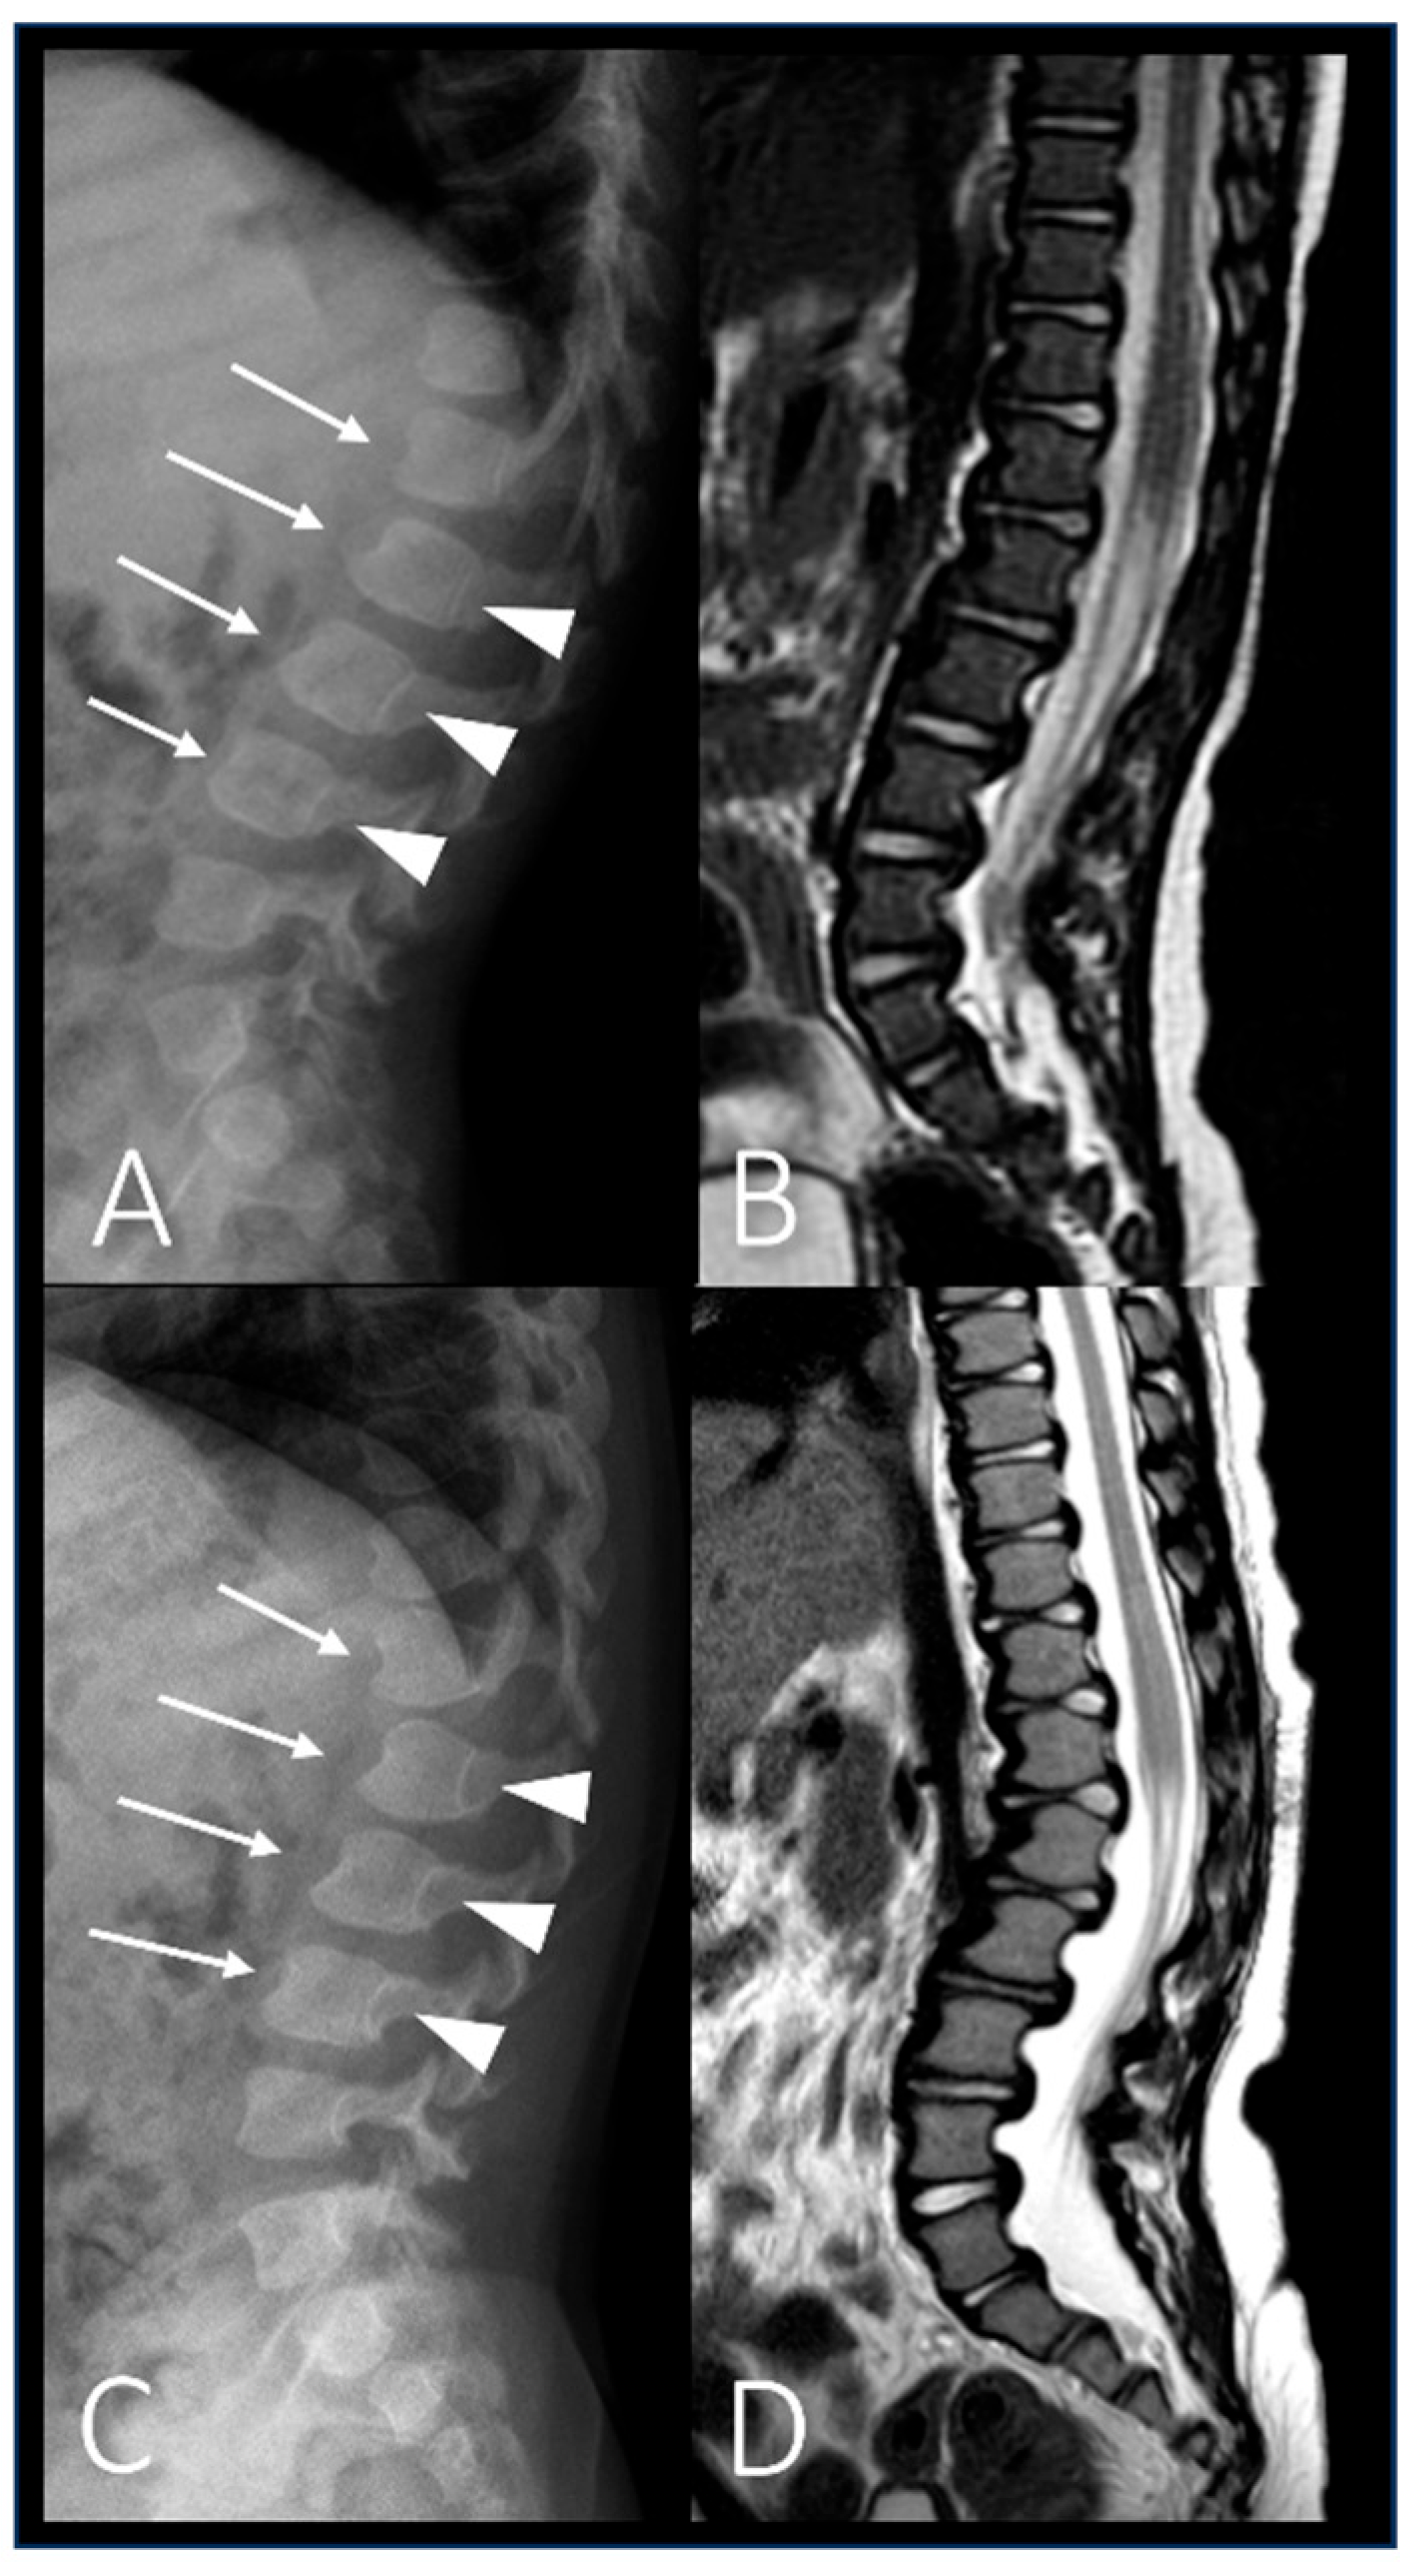

| P2 (MPSII) | Baseline | RX and MRI | Spine | Vertebral body deformities; posterior bulging of the intervertebral discs. |

| After 6 years of ERT | RX and MRI | Spine | Thoracolumbar kyphosis; anterior beaking and posterior scalloping of vertebral bodies. | |